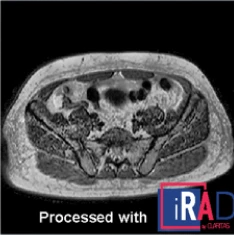

Processado com iRAD

Otimização de imagens de RM com melhoria de resolução, redução de artefatos e melhor definição de tecidos moles, proporcionando maior confiança diagnóstica em todas as sequências.

Processado com iRAD